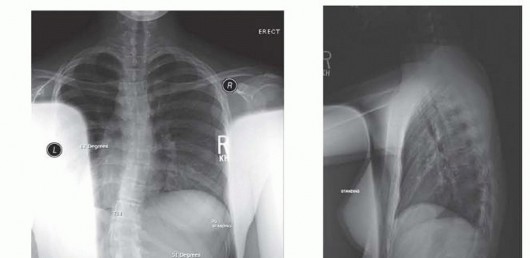

FIG 1A • Preoperative AP radiograph illustrating a 51-degree left lumbar curve, highlighting the coronal plane deformity.

FIG 1B • Preoperative lateral radiograph of the same patient, allowing assessment of sagittal alignment.